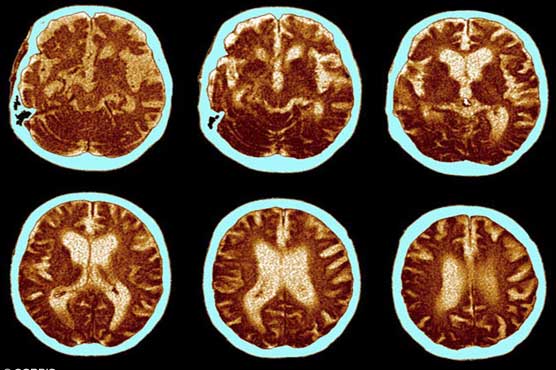

Collinge and colleagues, "very much to our surprise," found that seven of the eight had brain deposits of Alzheimer s-linked amyloid beta (Abeta) fragments -- with four of them having high concentrations.

Strikingly the patients were 36-51 years old, whereas such deposits are normally seen in elderly people.

The study authors said the eight fatalities in the study did not have the full-blown features of Alzheimer s -- they were missing the "tangles" caused by a different protein called Tau.